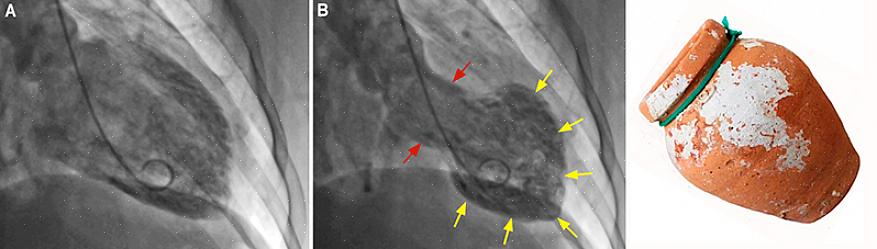

תסמונת הלב השבור, הידועה גם בשם Takotsubo cardiomyopathy, היא מחלת לב המתרחשת כאשר אדם סובל ממתח נפשי ופיזי. זה יכול להתבטא אצל אנשים בריאים אחרת.

זה קורה בגלל שהלב מפסיק לשאוב דם לאזור באיבר זה, וכתוצאה מכך הוא הופך למשותק משהו. לכן, הוא מייצר הפרעה לבבית למרות העובדה ששאר הלב ממשיך לתפקד כראוי.